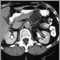

Liver metastases, CT scan